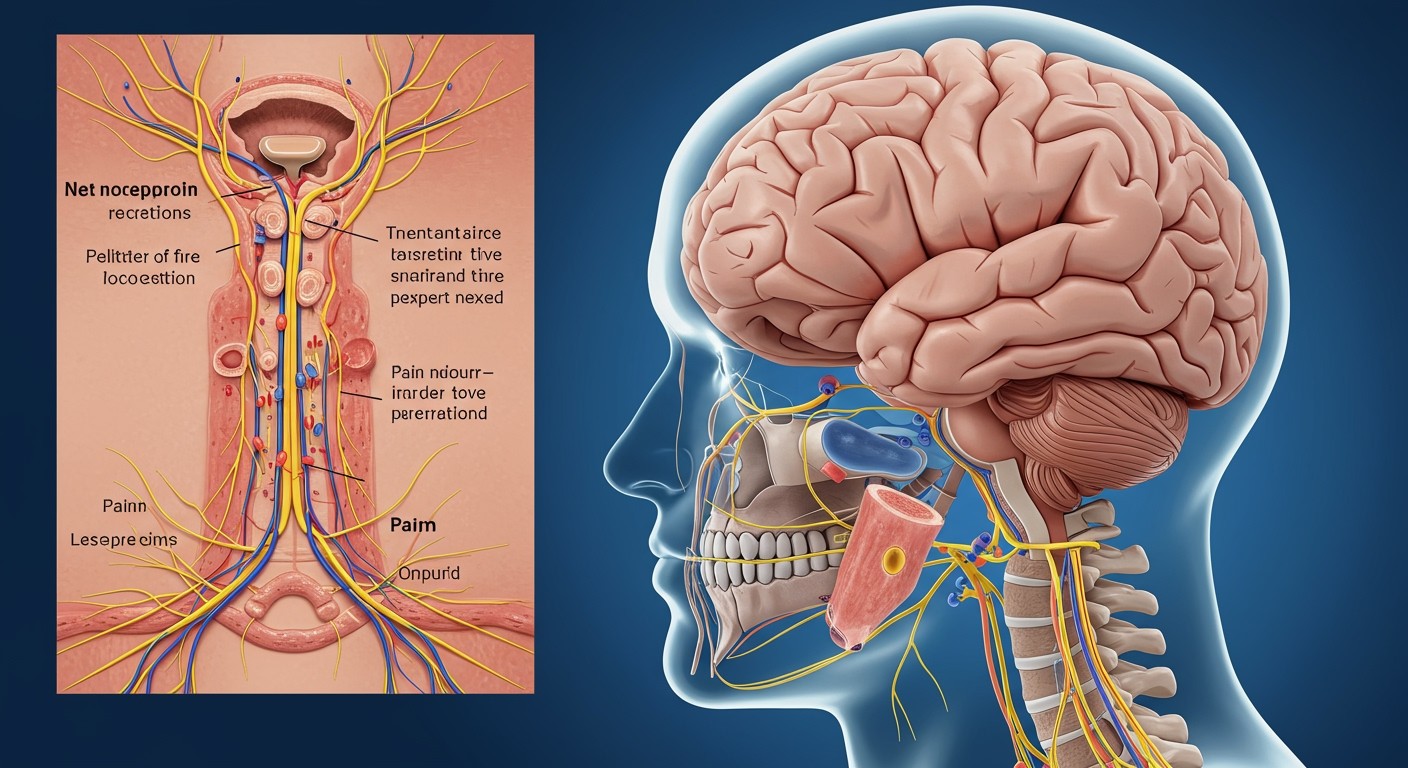

A nocicepció folyamata: A perifériától az agyig

Bár az agy maga nem rendelkezik fájdalomreceptorokkal (nociceptorokkal), a fájdalom érzékelése egy összetett folyamat, mely a periférián kezdődik és az agyban csúcsosodik ki. Ezt a folyamatot nocicepciónak nevezzük.

A nocicepció első lépése a nociceptorok aktiválódása a test különböző részein. Ezek a speciális idegvégződések érzékelik a potenciálisan káros ingereket, mint például a hő, a nyomás vagy a kémiai anyagok. A nociceptorok többnyire a bőrben, izmokban, ízületekben és belső szervekben találhatók.

Miután a nociceptorok aktiválódtak, elektromos jeleket generálnak, melyek az idegrostokon keresztül a gerincvelőbe jutnak. Ezek az idegrostok két fő típusa az A-delta és a C rostok. Az A-delta rostok vastagabbak és gyorsabban vezetik az impulzust, ezért éles, lokalizált fájdalmat közvetítenek. A C rostok vékonyabbak és lassabban vezetik az impulzust, tompa, égő fájdalmat közvetítve.

A gerincvelőben a fájdalomjelek átkapcsolódnak a második neuronokra, melyek az agy felé továbbítják az információt. Ez a folyamat magában foglalja a neurotranszmitterek, például a glutamát és a substance P felszabadulását, melyek serkentik a következő neuront.

A fájdalomjelek a gerincvelőből az agytörzsbe jutnak, majd onnan különböző agyi területekre, beleértve a talamuszt, a szomatoszenzoros kérget, a limbikus rendszert és a prefrontális kérget. A talamusz egyfajta „reléállomásként” funkcionál, szétosztva a fájdalomjeleket a többi agyi terület felé.

A szomatoszenzoros kéreg felelős a fájdalom lokalizációjáért és intenzitásának érzékeléséért. A limbikus rendszer, amely érzelmekkel és memóriával kapcsolatos, befolyásolja a fájdalom érzelmi komponenseit. A prefrontális kéreg pedig a fájdalom kognitív értékelésében és a viselkedési válaszok megtervezésében játszik szerepet.

Az agy nem maga érzékeli a fájdalmat, hanem értelmezi a perifériáról érkező jeleket. A fájdalom tehát egy komplex, agyi konstrukció, mely a szenzoros bemenet, az érzelmi állapot és a korábbi tapasztalatok alapján alakul ki.

A fájdalom továbbítása a gerincvelőn keresztül

Bár az agy maga nem érez fájdalmat, a fájdalomérzet elengedhetetlen ahhoz, hogy felismerjük a sérüléseket és reagáljunk rájuk. A fájdalom útja a perifériás idegrendszerben kezdődik, ahol speciális receptorok, az úgynevezett nociceptorok érzékelik a potenciális szövetkárosodást.

Ezek a receptorok azután elektromos jeleket generálnak, melyek az idegrostokon keresztül a gerincvelőbe jutnak. A gerincvelő egyfajta reléállomásként funkcionál, ahol a fájdalomjelek feldolgozásra kerülnek és továbbítódnak az agy felé. Itt történik az elsődleges szűrés és moduláció is, ami befolyásolja a fájdalom intenzitását.

A gerincvelőben a fájdalomjelek átkapcsolódnak egy másik idegsejtre, amely az agytörzsbe és a talamuszba szállítja az információt. A talamusz egy központi reléállomás az agyban, amely a szenzoros információkat a megfelelő agykérgi területekre irányítja. Az agykérgi területek felelősek a fájdalom lokalizálásáért, intenzitásának megítéléséért és az érzelmi válaszokért.

A gerincvelő kulcsszerepet játszik a fájdalom továbbításában és modulálásában, lehetővé téve az agy számára, hogy megfelelő módon reagáljon a potenciális veszélyekre.